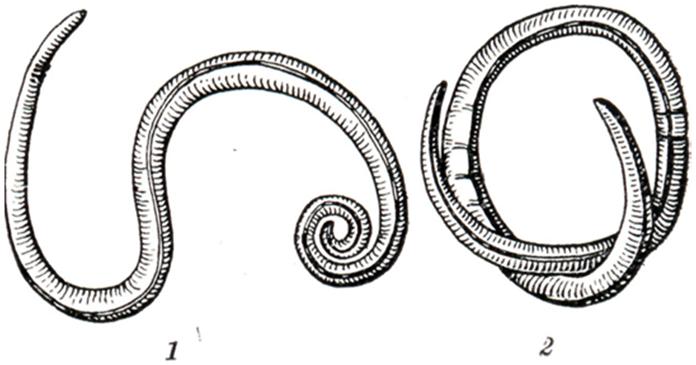

АскаридозАскаридоз (ascaridosis; греческое askaris, askaridos + - osis) — гельминтоз, вызываемый круглыми червями — аскаридами. У человека могут паразитировать несколько видов аскарид, из которых все, кроме Ascaris lumbricoides, являются облигатными паразитами животных и у человека в половозрелой стадии встречаются крайне редко. ЭтиологияВозбудитель — Ascaris lumbricoides — крупные раздельнополые гельминты (рис. 1). Размер самок 25—40 см, самцов —15—25 см. Головной конец снабжен тремя большими кутикулярными губами, окружающими ротовое отверстие. Хвостовой конец самки прямой с коническим придатком, самца — загнут на брюшную сторону. Яйца овальные (рис. 2), снабжены пятью оболочками, наружная из них толстая, фестончатая (белковой природы), прокрашивается пигментом фекалий в коричневый цвет. Встречаются яйца и без белковой оболочки. За белковой располагается трехслойная глянцевитая оболочка. Обе оболочки предохраняют зародышевую массу от механических повреждений. Внутренняя (тонкая) оболочка — липидная, полупроницаемая, задерживает соли и органические вещества, но проницаема для воды. Размер яиц 0,050-0,070 × 0,040— 0,050 мм. Аскариды могут продуцировать и так называемые неоплодотворенные яйца (яйцеклетки), имеющие неправильную форму, крупные размеры (0,050 — 0,106 × 0,040 — 0,050 мм) и лишенные зародышевой массы. Взрослые аскариды обитают в тонком отделе кишечника, где удерживаются, согнувшись дугой или свернувшись кольцом, упираясь в стенки кишки. Питаются пищевой кашицей, находящейся в кишечнике, и поверхностными слоями слизистой оболочки тонкой кишки. Самки после оплодотворения выделяют яйца на стадии одного бластомера, все развитие которых происходит в окружающей среде. Скорость развития зависит от условий температуры, влажности и состава почвы. Яйцо становится заразным после того, как сформировавшаяся в нем личинка совершит линьку и превратится в инвазионную личинку в чехлике.